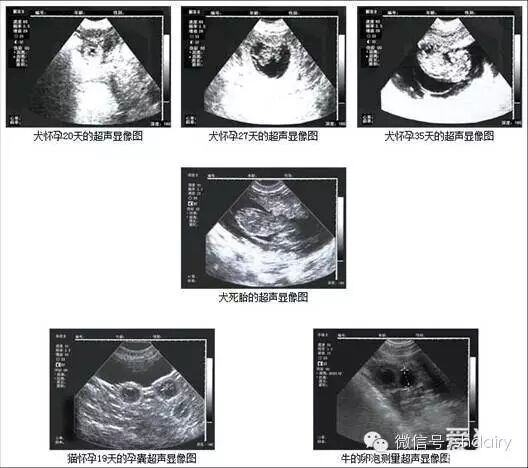

(3)验胎技术

早早孕试纸。

B超诊断